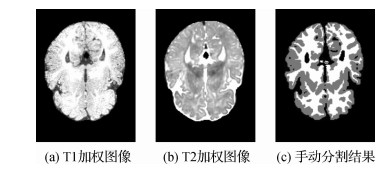

• 等强度婴儿脑MR图像分割的深度学习方法综述

等强度婴儿脑MR图像分割的深度学习方法综述

摘要:磁共振(magnetic resonance,MR)成像作为一种安全非侵入式的成像技术,可以提供高分辨率且具有不同对比度的大脑图像,被越来越多地应用于婴儿大脑研究中。将婴儿脑MR图像准确地分割为灰质、白质和脑脊液,是研究早期大脑发育模式不可或缺的基础处理环节。由于在等强度阶段(6~9月龄)婴儿脑MR图像中,灰质和白质信号强度基本一致,组织对比度极低,导致此阶段的脑组织分割非常具有挑战性。基于深度学习的等强度婴儿脑MR图像分割方法,由于其卓越的性能受到研究人员的广泛关注,但目前尚未有文献对该领域的方法进行系统总结和分析。因此本文对目前基于深度学习的等强度婴儿脑MR图像分割方法进行了系统总结,从基本思想、网络架构、性能及优缺点4个方面进行了介绍。并针对其中的典型算法在iSeg-2017数据集上的分割结果进行了对比分析,最后对等强度婴儿脑MR图像分割中存在的问题及未来研究方向进行展望。本文通过对目前基于深度学习的等强度婴儿脑MR图像分割方法进行总结,可以看出深度学习方法已经在等强度期婴儿脑分割中展现出巨大优势,相比传统方法在分割精度和效率上均有较大提升,将进一步促进人类人脑早期发育研究。

关键词:磁共振成像;等强度期;婴儿脑分割;深度学习;卷积神经网络